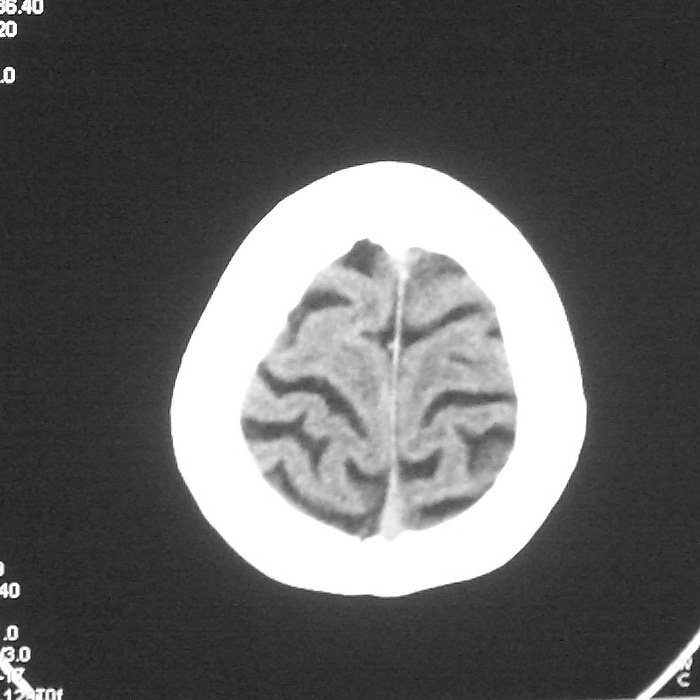

f,70y,口角歪斜、流涎、吐词不清三天

左侧大脑基底节区点状低密度影,边缘清楚,左侧腔梗或软化灶,没什么问题啊?

左侧半卵圆中心腔梗应当比较明确,右侧基底节好象不明显,不好说,做个mri明确吧

右侧基底,左侧半卵圆中心腔梗

1、右侧基底,左侧半卵圆中心腔梗。2脑萎缩。

左侧腔隙性梗塞灶,脑萎缩。

左侧基底节区示点状低密度灶,边界清楚,密度均匀,余所示无著变。

意见:腔隙性脑梗塞(左基底节区)

各位老师,报告这么写可以吗?右侧我没有看出来。

具体位置我认为应该写左侧放射冠腔梗

左侧半卵圆中心,右侧基底节腔梗。再加个脑萎缩吧